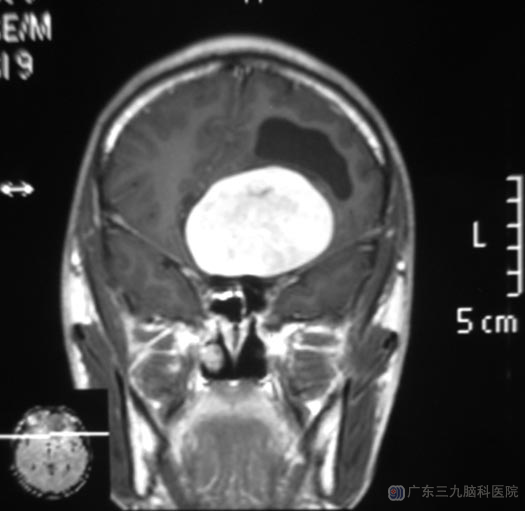

当地医院CT检查提示:前颅窝占位;广东三九脑科医院头颅磁共振检查提示病变大小约62.4mm×61.6mm×45.8mm。弟弟告诉综合神经外科的鲁明主任,四年前就出现嗅觉减退、鼻塞,以右侧为重,没有给予重视。

完善检查后,鲁明主任主刀,在全麻下行冠状切开左额入路前颅窝底肿瘤切除术。术中见肿瘤呈灰褐色,位于前颅窝底,质中,显微镜下分块全切,术中视神经、颈内动脉及其分支保护完好。术后,嗅觉较术前好转。病理结果:恶性黑色素瘤。

▲术前MR